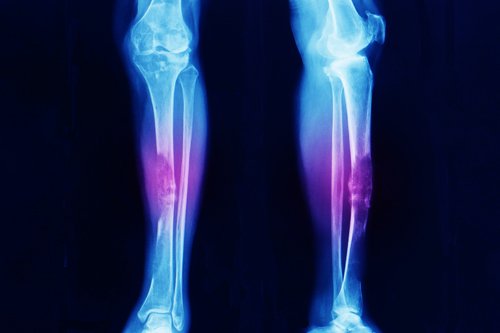

Bone Tumors are masses formed by abnormal cell growth in bones. They can be benign (non-cancerous) or malignant (cancerous). Benign tumors, like osteochondromas, nonossifying fibromas, and enchondromas, are usually not fatal but may require treatment if they cause issues. Malignant tumors, like osteosarcoma, are cancerous and may spread through the body. Causes are largely unknown but may include genetics, radiation, injuries, or rapid bone growth.

3. Imaging Tests: X-rays, CT scans, MRI, PET scans, and bone scans to locate and assess tumors.